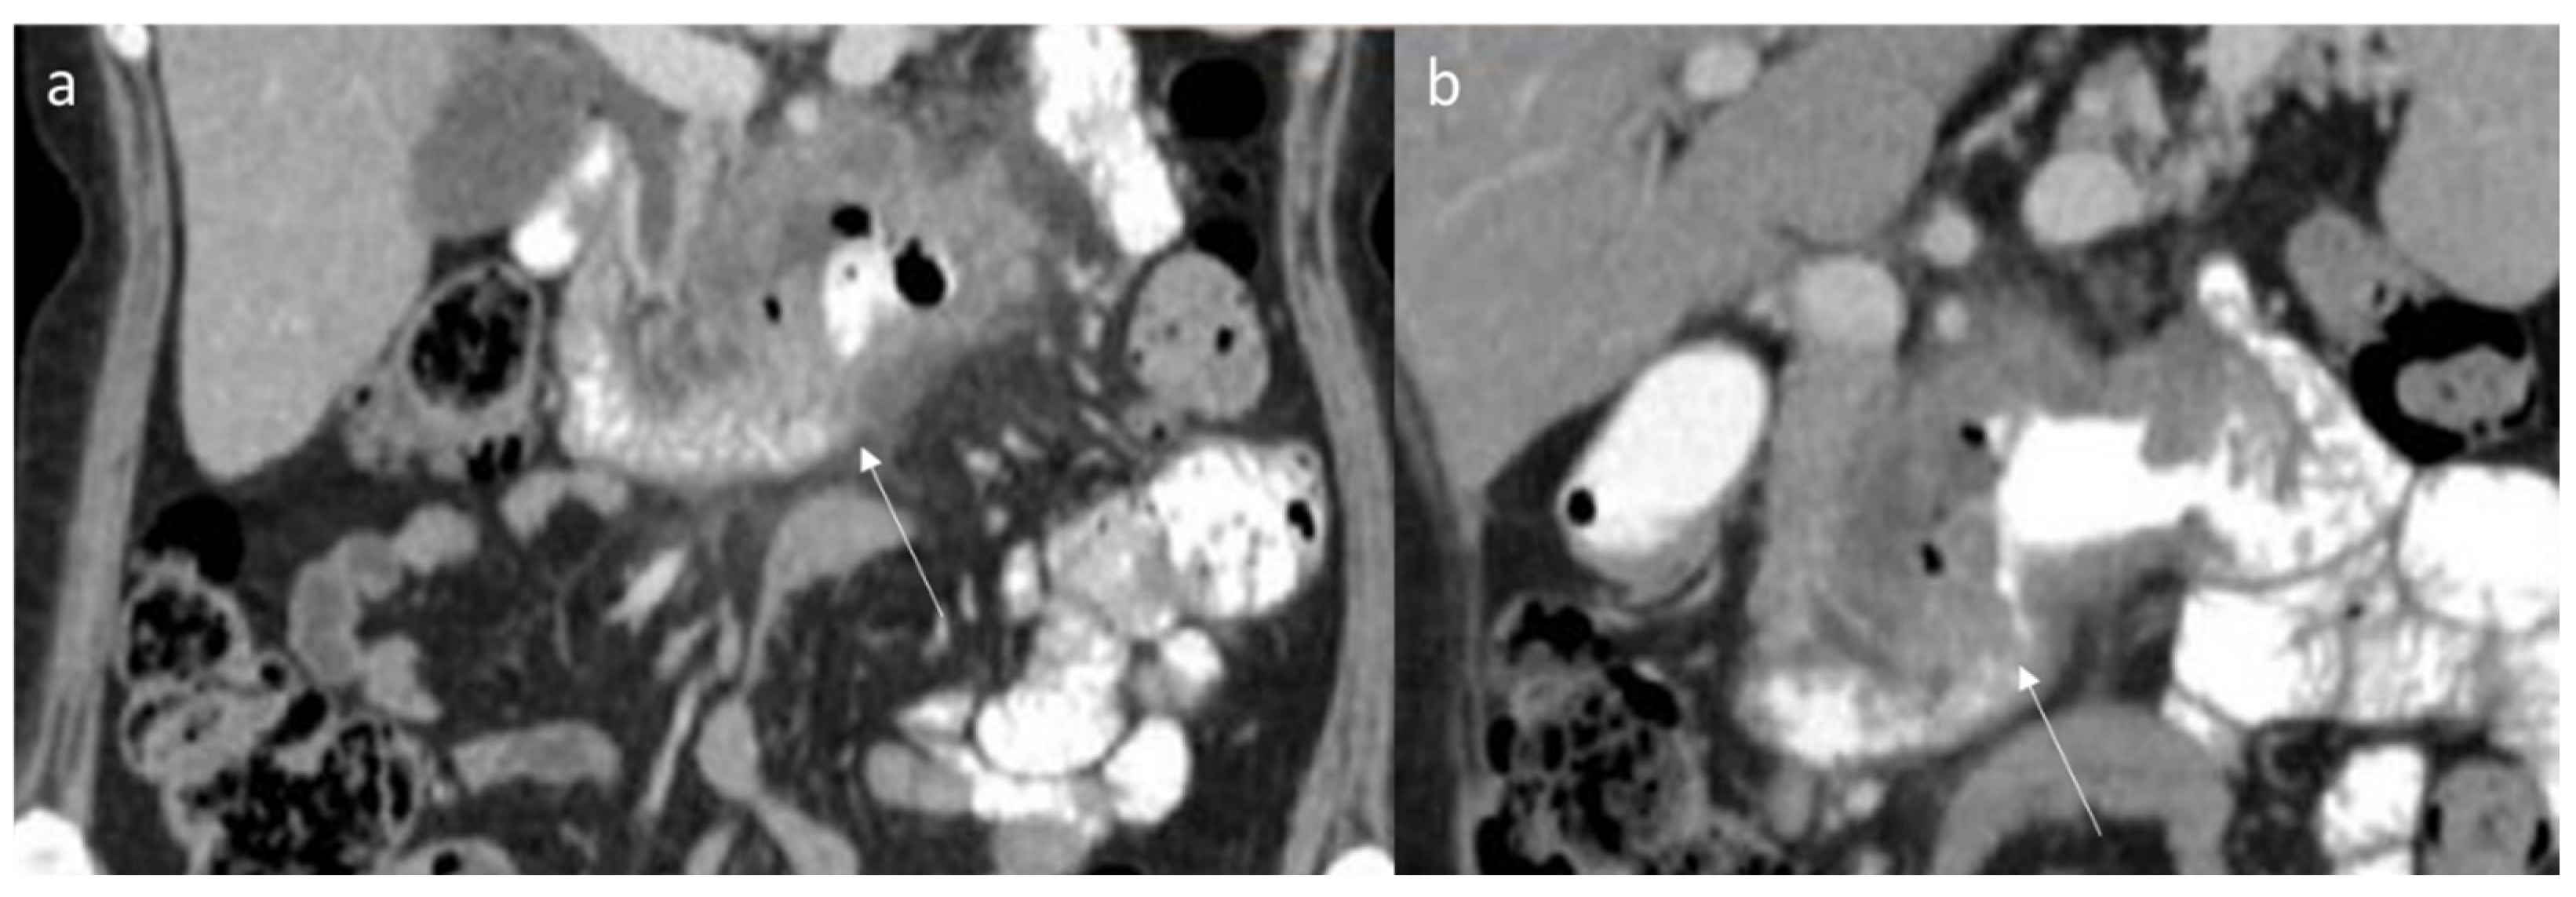

6. Computed Tomography Assessment

| Imaging Assessment [80,137] | The density of the lesions on CT imaging is uniform, and an enhanced scan can show uniform enhancement. Homogeneous signal is isointense in T1-W and hyperintense in T2-W | Inhomogeneous density on CT and signal intensity on MRI, due to necrosis and calcifications, with inhomogeneous contrast enhancement during contrast studies | CT features of desmoid tumors of the extremities exhibited a slightly low density, mild enhancement, unclear boundary and uneven enhancement after contrast administration. Their imaging features on MRI were a round or fusiform shape, unclear boundaries, uniform signal, uneven enhancement, “tree root” or “claw” infiltration and invasion of the neurovascular bundles | Inhomogeneous density on CT and long T1 and long T2 signals, T2 signal intensity higher than that of fat on MRI. Calcification or cystic necrosis |